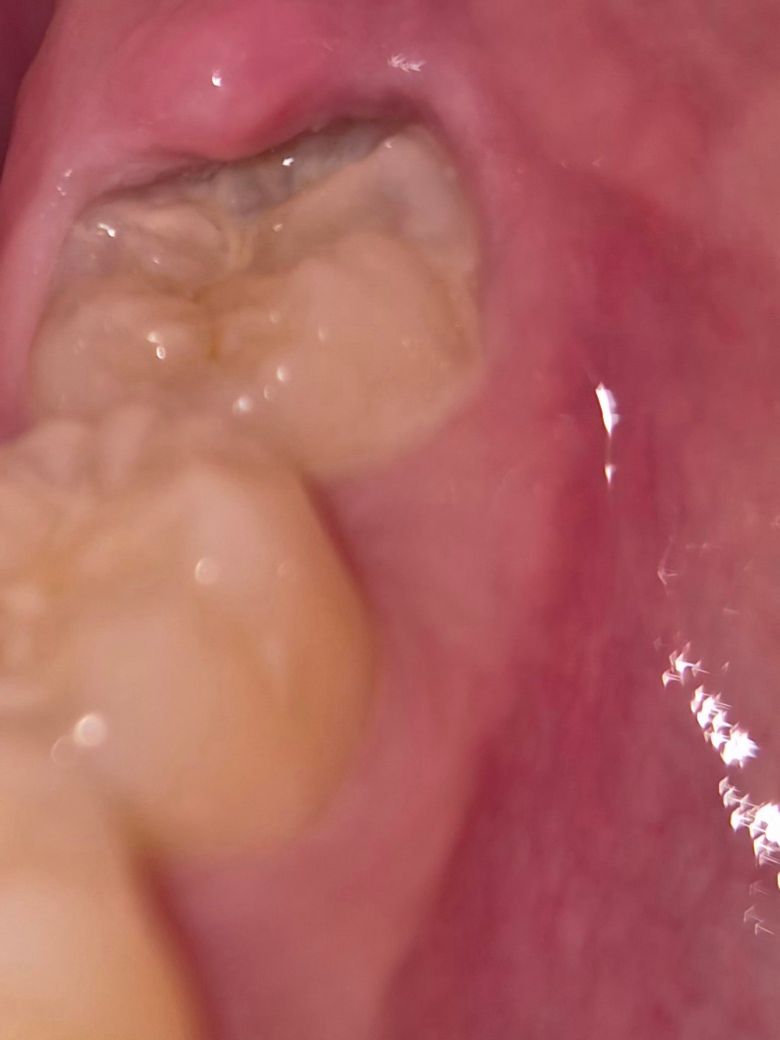

이거 썩은건가요..?? 사랑니 쪽이라 뽑는게 너무 무서운데 어쩌죠

부끄럽지만 치과 가기전에 확인하고 싶어서요ㅠㅠ

냄새도 나는것같고 인터넷에 증상 검색했더니 치실 하라고 하거나 치과 가라는데 저렇게 생겨먹어서 치실을 못하더라구요....

• 1번 째 사진

사랑니 부위가 관리가 안되다 보니 염증이 생긴거 같습니다. 일단은 잇몸치료를 해보시는게 좋을것같습니다.

충치는 지금 사진상으로는 특별히 관찰되진 않고 치석, 치태가 굉장히 많이 쌓여있습니다. 평소 양치질을 좀 더 꼼꼼히 해주고 치과에서 스케일링을 한번 해보면 좋을 것 같습니다. 해당 부위 치아 주변 잇몸이 부어있기 때문에 일단 잇몸을 가라앉히고 재평가 하면 될 것 같습니다.

사진만으로는 애매하지만 충치가 있어 보이며 치실할 필요 없고 사랑니는 발치를 하시는 것이 좋겠습니다.